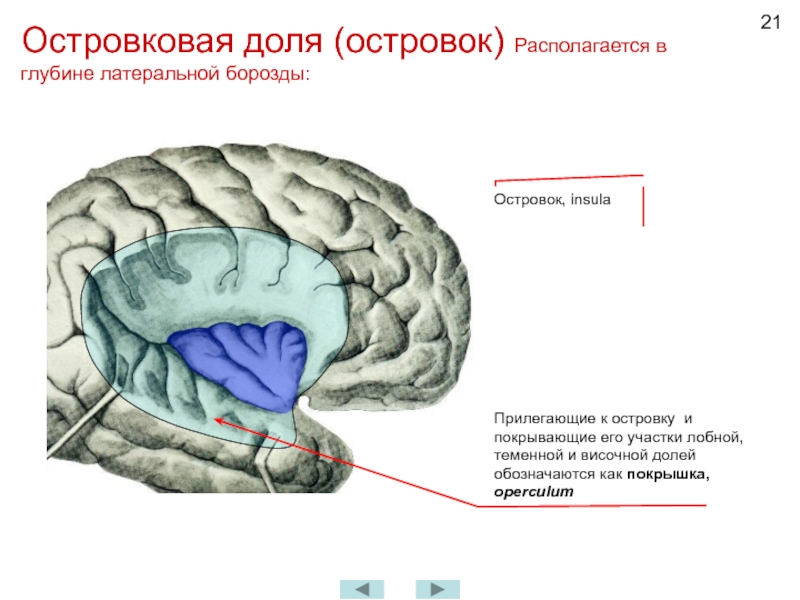

Анатомические снимки верхнелатеральной поверхности головного мозга